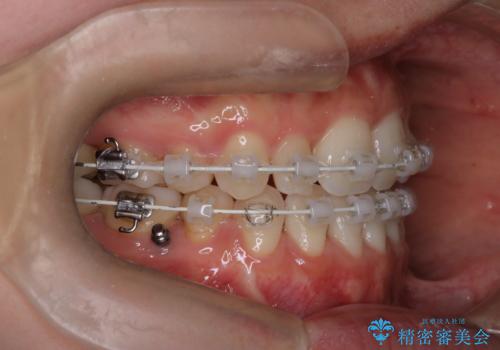

- 口元をさげたいという主訴で来院されました。4番の歯を4本抜歯し、遠心移動とIPRをしました。右上2番が矮小歯のため見た目を重視するならクラウンの提案をしましたが、そのままでの治療を希望されました。

矯正治療の最終段階でスペースクローズにやや時間がかかりましたが、前歯が下がったことで口元の位置も下がりきれいになりました。